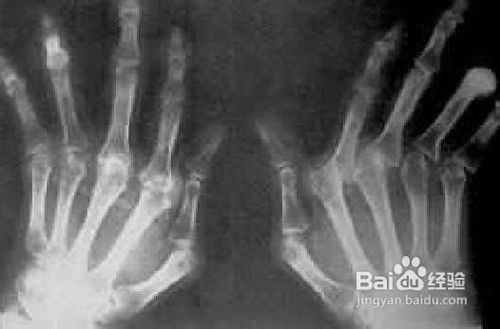

痛风是由单钠尿酸盐沉积所致的晶体相关性关节病,与嘌呤代谢紊乱和(或)尿酸排泄减少所致的高尿酸血症直接相关,特指急性特征性关节炎和慢性痛风石疾病。